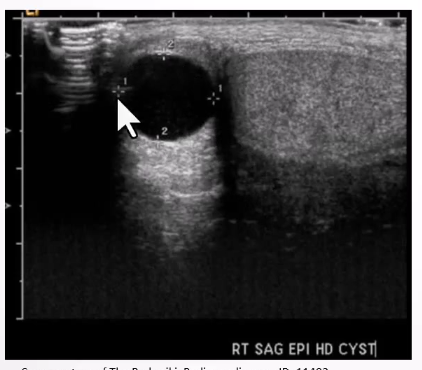

Epididymal Cyst:

Ultrasound Appearance:

Well-defined anechoic lesion within the epididymis

Shows posterior acoustic enhancement.

Large cysts can displace the testis